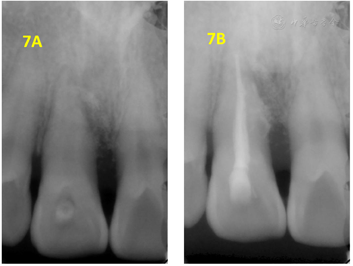

翻瓣探查术后3个月复查(2018年2月28日):检查:11舌侧暂封在,叩痛(-),Ⅰ-松动,唇侧龈退缩3 mm,牙龈充血,近中唇侧位点PD5 mm,余位点2~3 mm,见图6。X线片示:11近中骨质吸收已大部分恢复,见图7A。处置:11上橡皮障,3%次氯酸钠+生理盐水冲洗,干燥,Iroot SP+牙胶尖根充完成根管治疗见图7B,酸蚀粘接,树脂充填,调

,修形,抛光,完成治疗。